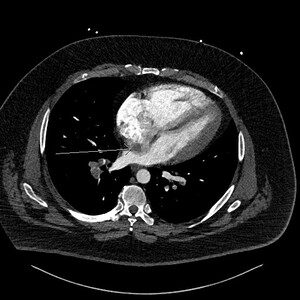

This prompted a re-evaluation of the initial CTPA by a specialist cardiothoracic radiologist. The following figures show selected images from the CTPA. Figure 1 is an axial slice demonstrating the already known bilateral filling defects within branches of the pulmonary arterial system, consistent with PEs (stars).

Figure 2 is an axial slice which shows a well-defined, round, homogenous and low attenuation filling defect (long white arrow) in the right atrium (RA) positioned adjacent to the interatrial septum (IAS). The filling defect is visible in the RA even despite the contrast mixing artefact in the RA chamber, the aforementioned features indicated the presence of a structure within the RA chamber, in this instance thrombus.